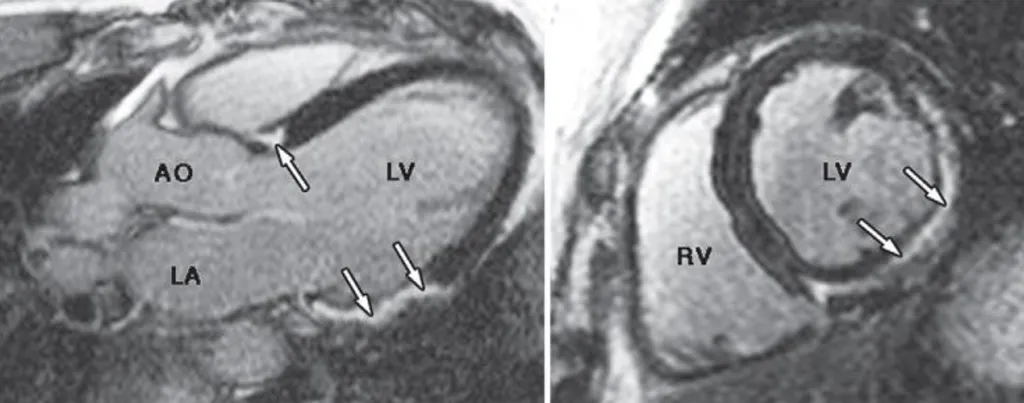

【114-1 醫學(三) 第8題】47 歲男性,曾頭暈昏倒多次,心電圖檢查顯示多發性心室期外收縮。磁振造影發現左心室較大,下壁及下外側壁收縮功能較差,顯影劑注射後,磁振造影出現顯影劑延遲增強(late gadolinium enhancement, LGE),如附圖所示。下敘述何者錯誤?

詳解

破題關鍵

這題的解題核心在於辨識心臟磁振造影(CMR)中「顯影劑延遲增強」(LGE)的影像特徵,並區分不同心臟疾病的LGE模式,同時要了解心肌水腫在MRI上的表現。圖片中箭頭所指的亮白色區域,就是LGE,它位於心肌的中外層,而非心內膜下。

選項拆解